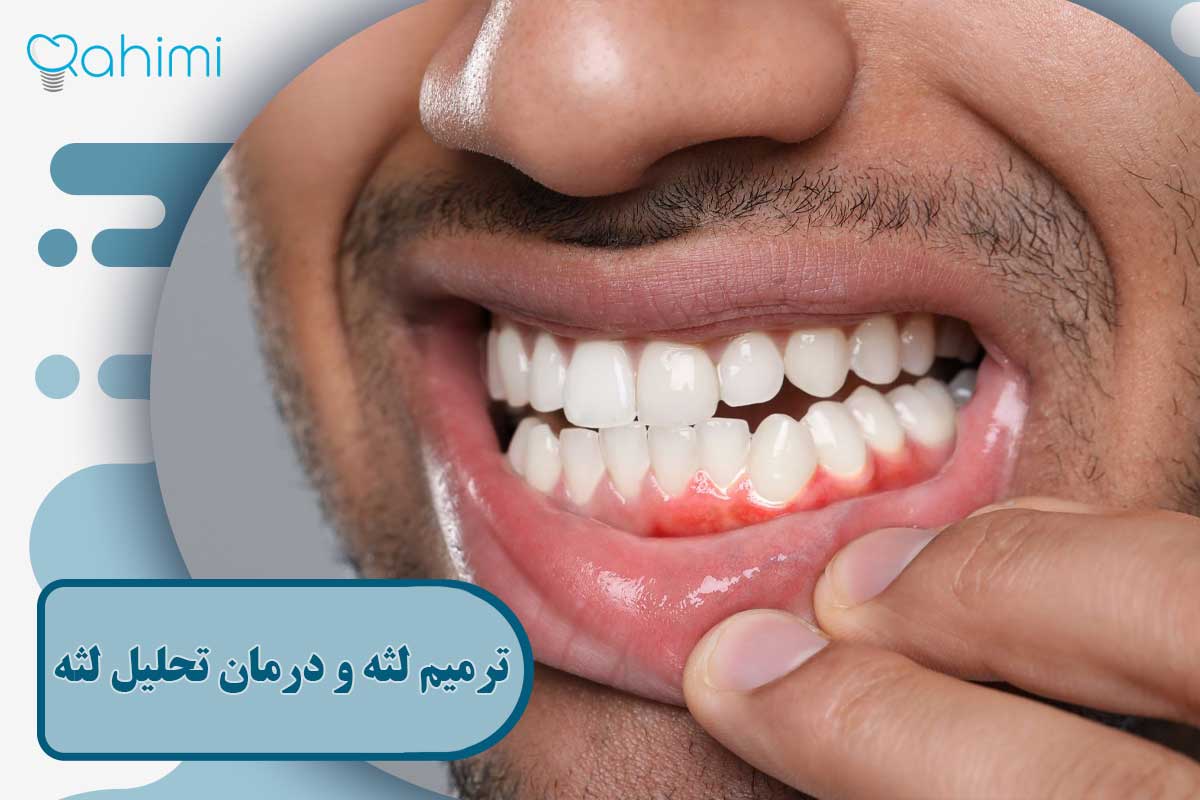

لثه سالم معمولاً این ویژگیها را دارد: رنگ صورتی کمرنگ تا مرجانی، بافت سفت و متراکم، حاشیه منظم و یکنواخت اطراف دندان و بدون خونریزی هنگام مسواکزدن. حاشیه لثه، تا ناحیه اتصال مینای دندان و ریشه را بهطور کامل میپوشاند و در لبخند، «قاب طبیعی» برای دندانها ایجاد میکند. در مقابل، لثه تحلیلرفته ممکن است اینگونه به نظر برسد:

- عقب رفتن حاشیه لثه و بلندتر بهنظر رسیدن دندان

- دیده شدن بخشی از ریشه که رنگ زردتر نسبت به تاج دارد

- ناهموار شدن خط لثه بین دندانها

- حساسیت، سوزش، یا تیرکشیدن دندانها

- گاهی خونریزی هنگام مسواک یا نخ دندان

از نظر عملکردی هم این تفاوت مهم است: لثه سالم مانند یک «مانع دفاعی» اطراف دندان عمل میکند، ولی وقتی تحلیل میرود، این سد دفاعی شکسته شده و راه برای تجمع باکتریها، التهاب و از بین رفتن استخوان باز میشود.